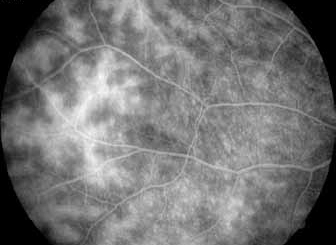

L’angiographie à la Fluorescéine

L’angiographie à la fluorescéine est un examen capital car elle permet de faire le bilan de l’atteinte rétinienne, et de retrouver des anomalies infra cliniques dans 6% des cas à type de vascularites rétiniennes (figure 4).

Par ailleurs l’angiographie peut objectiver, un œdème maculaire (figure 5)